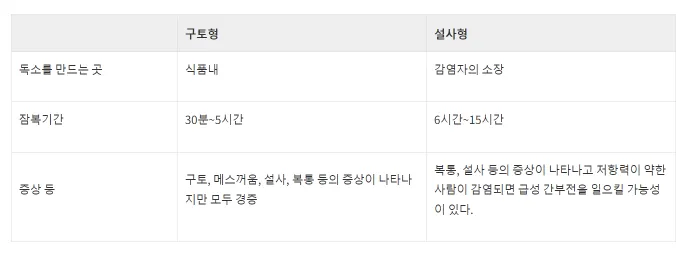

세레우스균으로 인한 식중독은 음식에서 105CFU/g 이상 존재할 때 발생합니다. 증상에 따라 ‘구토형’과 ‘설사형’의 2종류가 있습니다. 특히 국내에서는 ‘구토형’의 사례가 많이 발생하는 편입니다. 구토형 식중독은 균이 식품에서 생산한 구토를 일으키는 장독소(cereulide, 셀레우리드)를 섭취하면서 발생합니다. 잠복기는 1~6시간 정도로 짧으며, 합병증이나 발열 증상은 다행히 일어나지 않습니다.

한편, 국내에서는 사례는 적지만, 설사형 식중독에서는 식품과 함께 섭취한 균이 인간의 소장 안에서 증식하면서 생산되는 독소가 설사를 일으키는 것으로 발생합니다. 설사형은 구토형보다 독소를 생산하는 기간이 길어서 잠복기 또한 조금 더 긴 편입니다. 48시간 이내에 설사와 복통을 일으키며 하루 이상 이런 증상이 이어집니다.